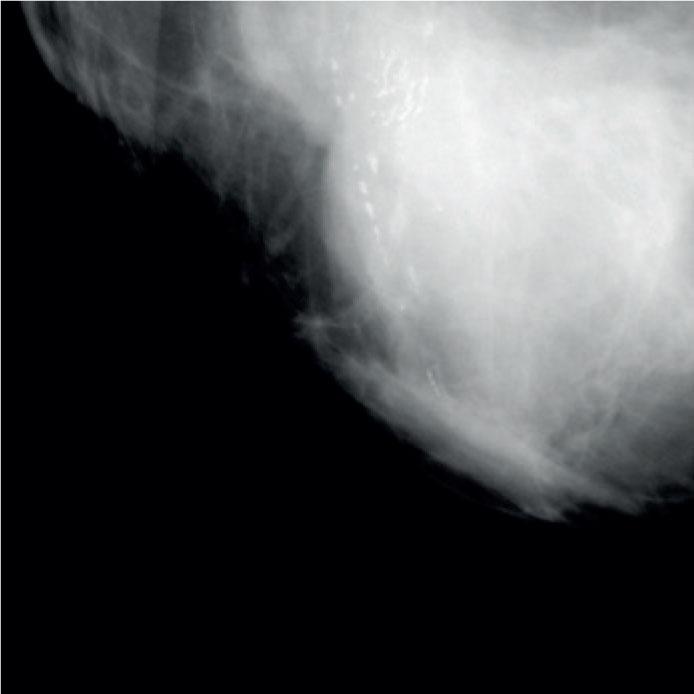

Powdery microcalcifications (cotton ball-like, indistinct, amorphous).

Crushed stone-like microcalcifications (pleomorphic).

Casting-type microcalcifications (linear, branching).